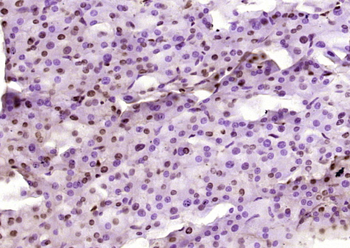

100 μl, 200 μl, 50 μl - RORC Rabbit Polyclonal Antibody [orb6888]Featured

FC, ICC, IF, IHC-Fr, IHC-P, WB

Human, Mouse, Rat

Bovine, Canine, Equine, Gallus, Porcine, Rabbit

Rabbit

Polyclonal

Unconjugated

50 μl, 100 μl, 200 μl - Featured